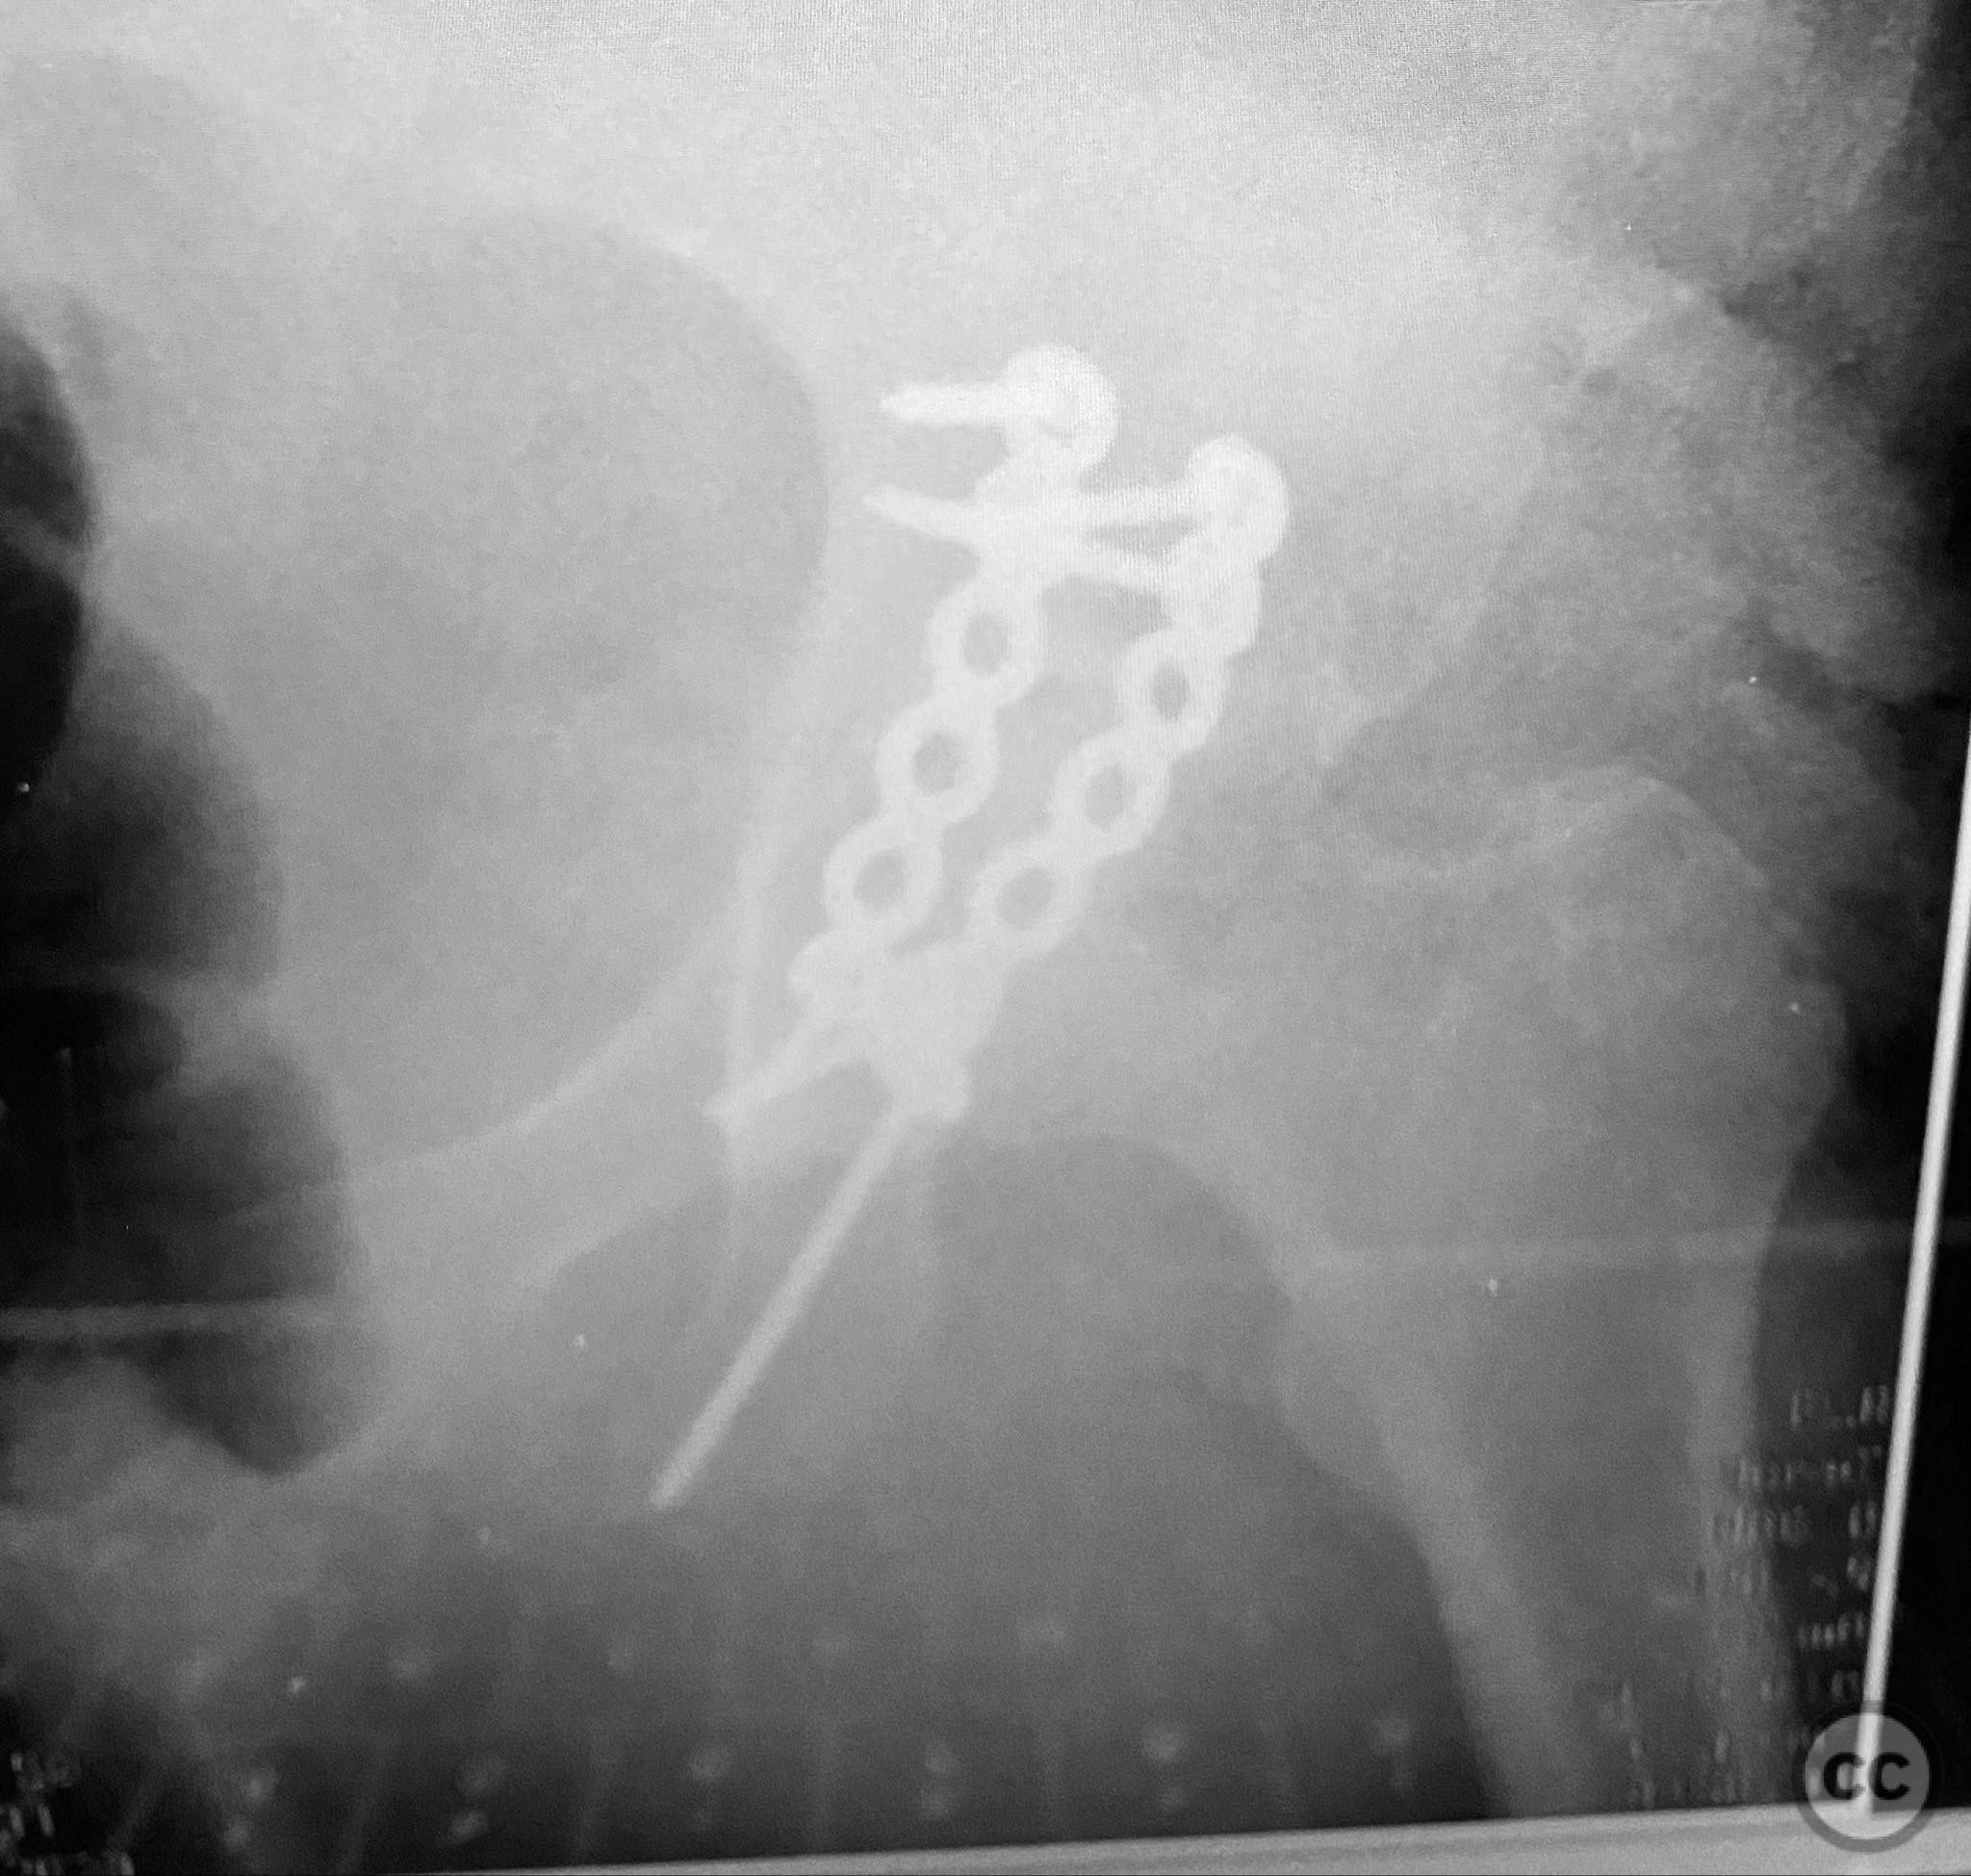

Clinical and radiological findings:  The patient is morbidly obese and sustained an unstable, displaced posterior column/posterior wall (PC/PW) acetabular fracture. Axial computed tomography images revealed a 2x2x1.5 cm pyramidal chondrocancellous articular fragment wedged in the fracture plane near the incisura ischiadica major (greater sciatic notch). Surface-rendered reconstructions further delineated the fracture morphology and fragment position. Obesity was noted to complicate all aspects of management, including anatomical localization, intraoperative imaging, and soft tissue handling.

Anatomical surgical approach:  A standard Kocher-Langenbeck approach was performed. The incision was made along the posterior aspect of the coxa, centered over the greater trochanter and extending distally along the femoral shaft. Subcutaneous adipose tissue was dissected to expose the fascia lata, which was incised in line with the skin incision. The gluteus maximus was split in line with its fibers, and the short external rotators (piriformis, obturator internus, gemelli) were identified and retracted or released as necessary to expose the posterior column and wall of the acetabulum. The sciatic nerve was identified and protected throughout. The fracture site was exposed, and the wedged chondrocancellous fragment was retrieved from the region adjacent to the incisura ischiadica major. Anatomic reduction of the articular fragment, posterior column, and posterior wall was achieved, followed by fixation with contoured plates and screws.

Morbid obesity significantly complicated intraoperative exposure, anatomical landmark identification, retraction, and fluoroscopic imaging. A 2mm pin placed under C-arm guidance facilitated accurate identification of the femoral shaft for limb positioning. Retrieval of the intra-articular chondrocancellous fragment required careful dissection near the greater sciatic notch. After reduction of all fragments, contoured plates and screws were applied to maintain stability. Postoperative imaging confirmed accurate reduction and appropriate implant placement. Wound management strategies were employed to mitigate increased risk of complications associated with obesity.

Orthopaedic implants used:   Contoured reconstruction plates; cortical screws